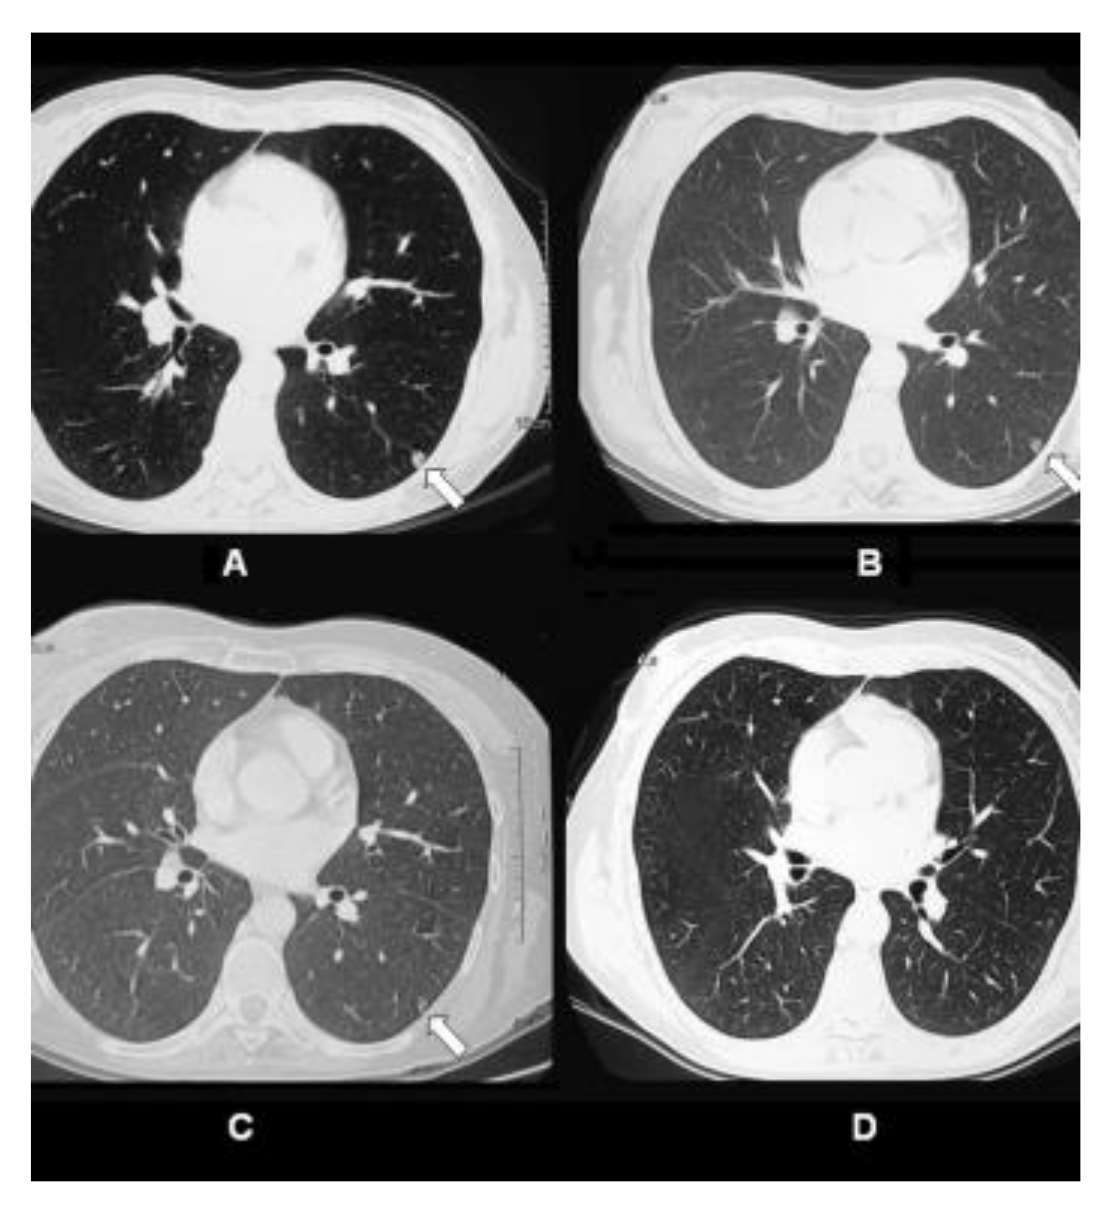

Case Highlight: In the one patient who achieved complete response all her pulmonary metastases disappeared. The patient was a 47-year old female diagnosed with stage IV breast cancer. She had received prior chemotherapy with AC (doxorubicin/cyclophosphamide) for 4 cycles, paclitaxel for 3 cycles, capecitabine plus ixabepilone for 3 cycles, and hormonal therapy with tamoxifen. However, she was resistant to these therapies. The patient received 4 treatments of ablation + IP-001 in total. Clinical observations before ablation + IP-001 showed that the sizes of the two tumors in the right breast of the patient were 6 × 4.5 cm and 2 × 2 cm. Metastatic nodules were observed in both lungs. Figure 1 shows the gradual regression, and subsequent elimination, of one of the patient’s lung metastases located in the left lung (indicated by arrow), before, during, and after ablation + IP-001.

Figure 1.

CT scans of pulmonary metastatic nodule in the left lung of 47-year-old female patient with stage IV breast cancer treated by laser ablation and IP-001 application. (A) CT scans of the patient taken before the first treatment. Small metastatic nodule was located in the left lung of the patient (indicated in arrow). (B) CT scans taken 1 week after the first treatment. (C) CT scans taken 2.5 months after the first treatment. (D) CT scans taken 12 months after the first treatment. This figure is reproduced from [35], with permission by the Royal Society of Chemistry and Owner Societies.

The anecdotal results from this investigator-initiated trial in patients with advanced and metastatic breast cancer, suggest a possible abscopal effect. Considering these were no-option patients, who have failed all the available treatment modalities, the effect of IP-001 was promising. Furthermore, the combination of local tumor ablation and application of IP-001 had an apparent impact on untreated, distant metastases (abscopal effect). Shown in Figure 1 are the images of a patient’s lungs after the treatment. Within a year after the treatment of breast tumors, the lung metastases completely disappeared.